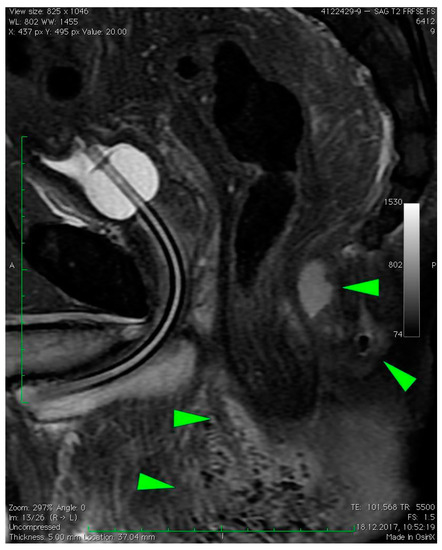

2.2. Radiologic Imaging

3. Case Presentation